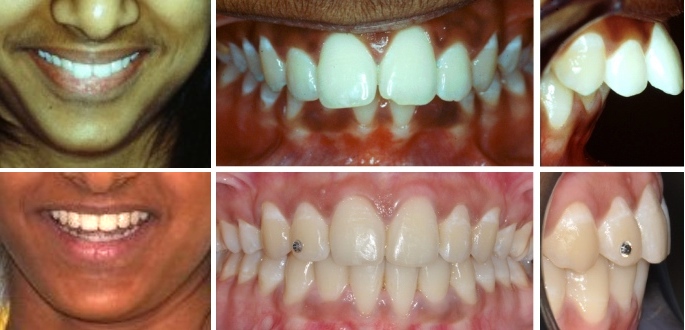

Fall 1: Vergrösserter Überbiss durch Unterkieferrücklage

Therapie: Nachtspange und festsitzende Spange